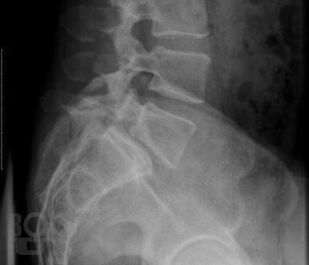

В учебном пособии, обобщающем многолетний педагогический опыт профессорско-преподавательского состава кафедры нервных болезней Военно-медицинской академии им. С. М. Кирова, с учетом данных современной литературы представлены сведения об анатомии, физиологии, заболеваниях и травмах спинного мозга. Отдельно рассмотрены вопросы эмбриогенеза, регенерации и аномалий развития спинного мозга. Пристальное внимание уделено топической диагностике спинальных поражений при сосудистых, инфекционных, демиелинизирующих, нейродегенеративных и системных заболеваниях. Специальные главы посвящены повреждениям спинного мозга при травмах, опухолях, воздействии экстремальных факторов, радиации и интоксикациях, а также современным методам исследования спинальной патологии и ее реабилитации. Издание иллюстрировано таблицами, схемами, рисунками и фотографиями, что облегчает восприятие и улучшает запоминание материала.